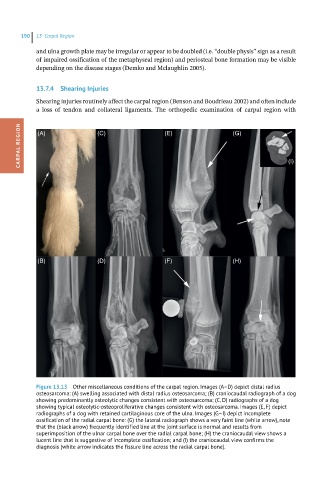

Figure 13.13 Other miscellaneous conditions of the carpal region. Images (A–D) depict distal radius

osteosarcoma: (A) swelling associated with distal radius osteosarcoma; (B) craniocaudal radiograph of a dog

showing predominantly osteolytic changes consistent with osteosarcoma; (C, D) radiographs of a dog

showing typical osteolytic-osteoproliferative changes consistent with osteosarcoma. Images (E, F) depict

radiographs of a dog with retained cartilaginous core of the ulna. Images (G–I) depict incomplete

ossification of the radial carpal bone: (G) the lateral radiograph shows a very faint line (white arrow), note

that the (black arrow) frequently identified line at the joint surface is normal and results from

superimposition of the ulnar carpal bone over the radial carpal bone; (H) the craniocaudal view shows a

lucent line that is suggestive of incomplete ossification; and (I) the craniocaudal view confirms the

diagnosis (white arrow indicates the fissure line across the radial carpal bone).